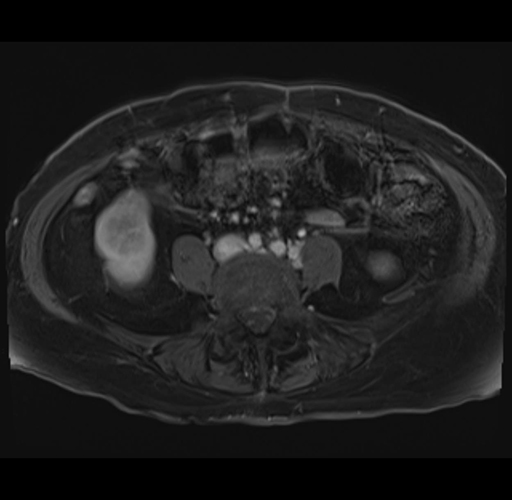

MRI T1